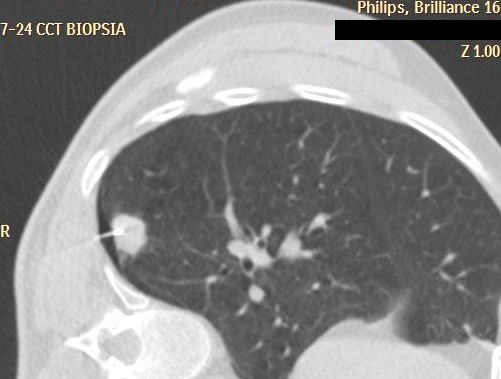

19.2.2.2. CT guided biopsy

Ideal method if the lesion is located either in the chest (figure 5.), mediastinum, retroperitoneum (figure 6.) or the pelvis.

Image

Figure 5. – CT guided thoracic biopsy